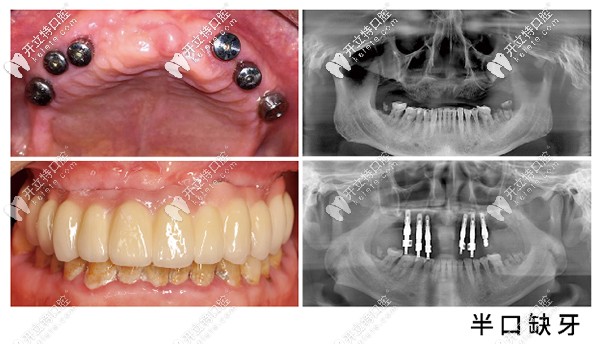

昆明美奧口腔半口種植牙案例

一般在昆明做半口種植牙價格在8萬以上,所以昆明美奧口腔收費(fèi)不算貴。咱們要知道種牙不僅要看價格,醫(yī)生技術(shù)也是考驗(yàn)后期使用長短的。